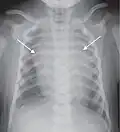

![A prominent thymus, which can give the impression of a widened mediastinum.[10]](./_assets_/X-ray_of_an_infant_with_a_prominent_thymus.jpg)